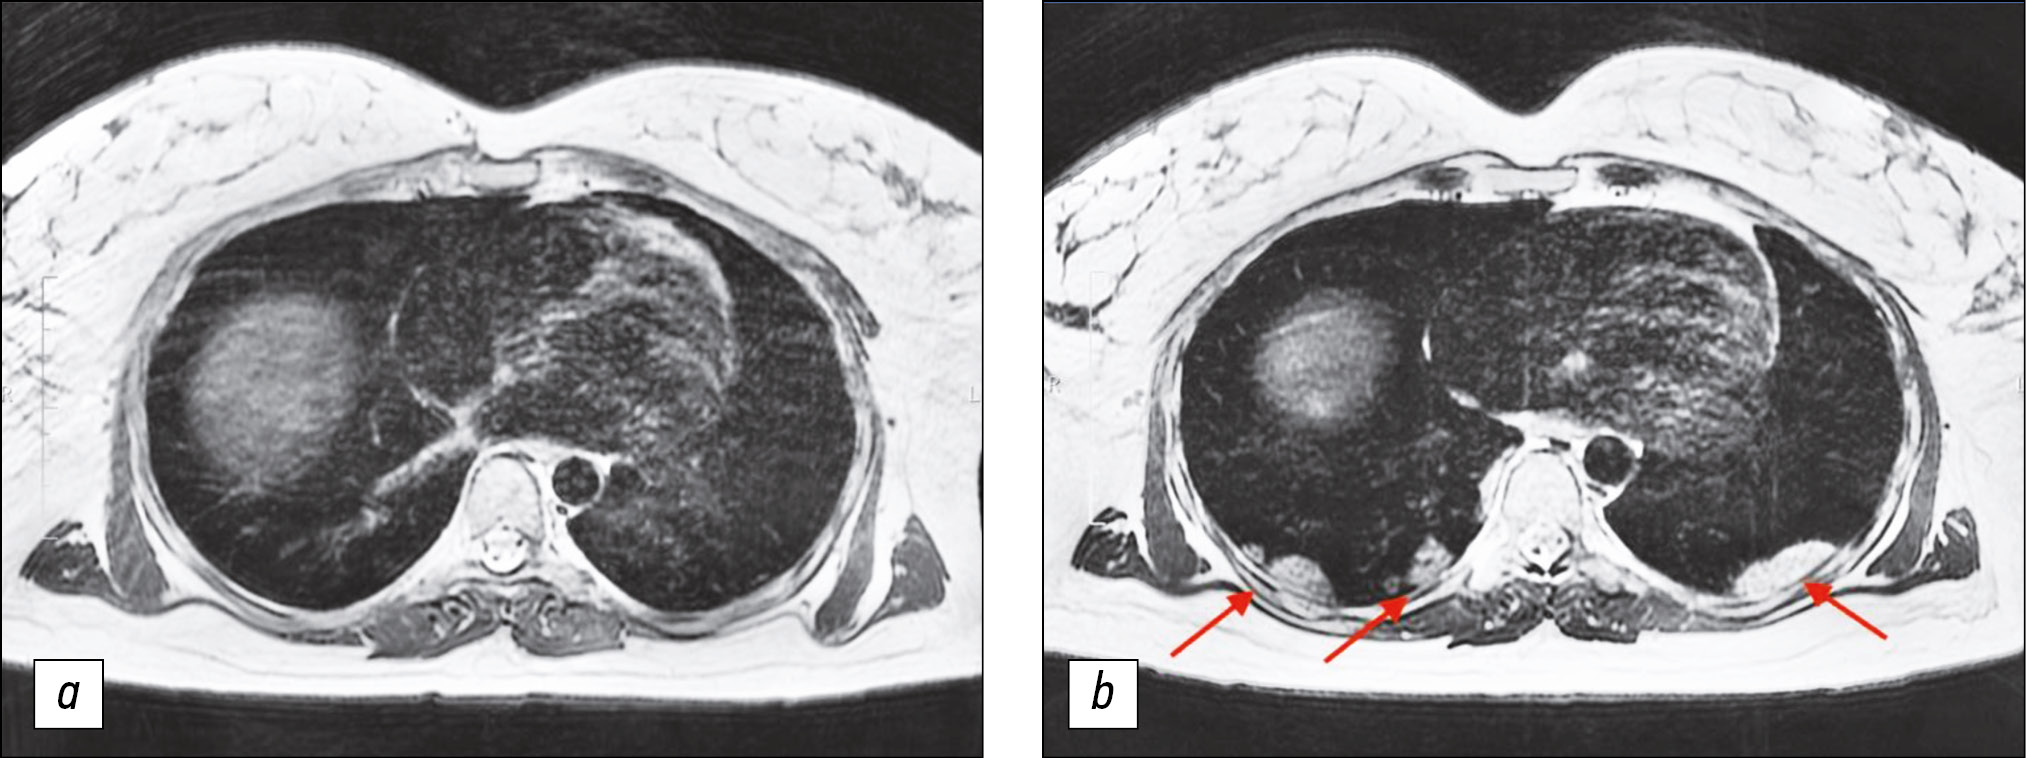

Lung MRI was performed 7 days later, because the condition did not improve during treatment, and dry, ineffective cough worsened. MRI performed that time revealed zones of infiltration (Figs. 1, 2) in the lower lobes of the lungs.

Figure 2. Chest magnetic resonance imaging, T2-weighted imaging single-shot fast spin echo: a) Primary examination, b) magnetic resonance imaging 7 days later. In Fig. 2b, consolidation zones in the lower right lung appeared as areas of hyperintense signal.